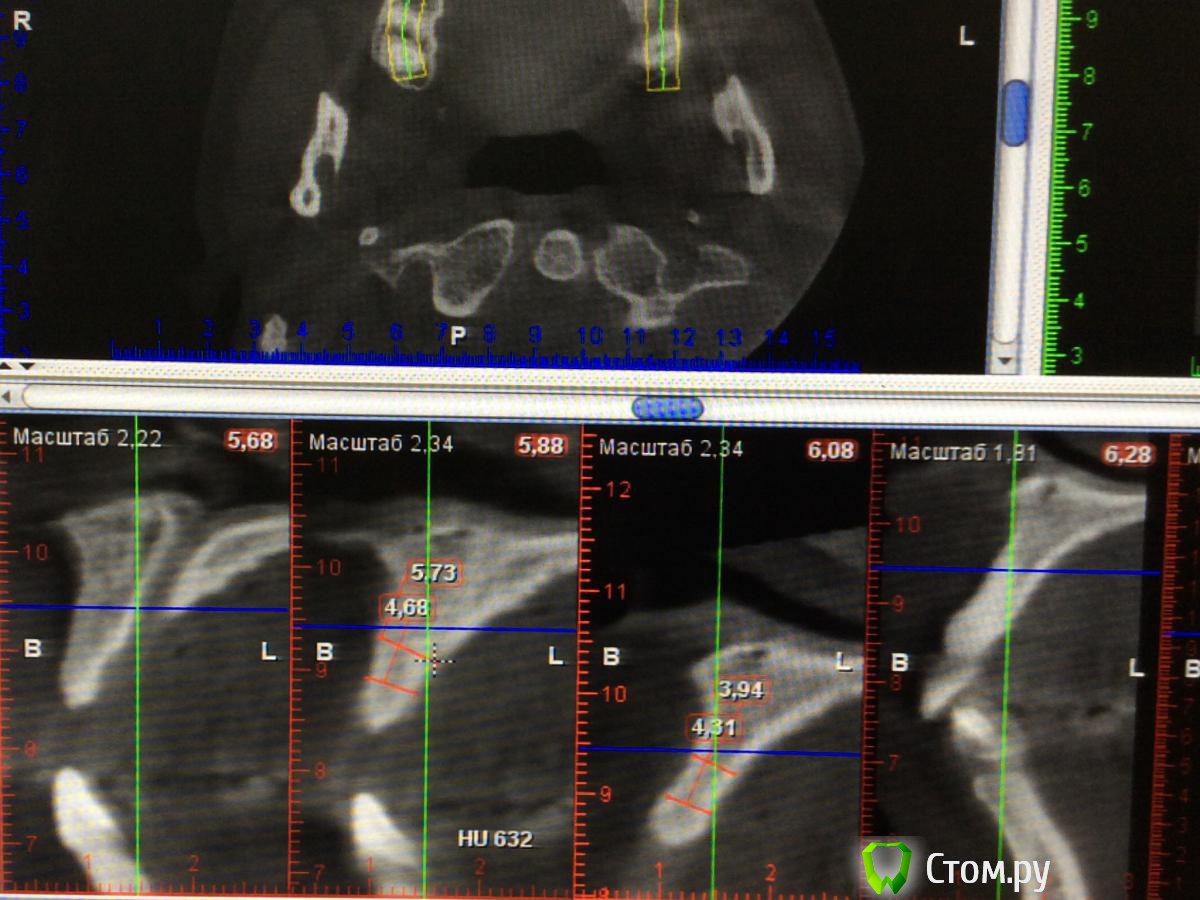

Chewey Опубликовано 23 июля, 2014 Поделиться Опубликовано 23 июля, 2014 (изменено) Какие варианты можно предложить ? Пациент 32 года, потерял 11,21. В следствии травмы, по высоте все неплохо, а вот объем в области 11. 2,6 мм , а в области 21,. 4.3мм. Изменено 23 июля, 2014 пользователем Chewey Ссылка на комментарий